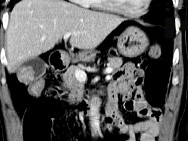

- 单项选择题男,45岁, 右季肋区疼痛,Murphy征阳性, B超提示胆囊息肉,CT所见如图, 最可能的诊断为 ( )